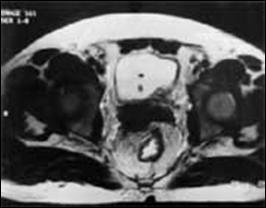

b). Neoplasm de col uterin, invaziv in vezica urinara

a. b.

a) Tumora de col uterin, invaziva in vezica urinara - pacienta s-a prezentat in anurie; b) Tumora de col uterin, operata (histerectomie totala + iradiere), recidivata, invadand vezica urinara si rectul - pacienta s-a prezentat cu hematurie